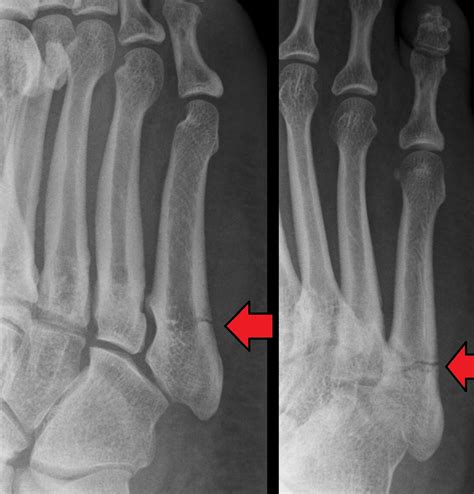

• Imaging Tests: X-rays are the most common imaging test used to diagnose fractures. However, hairline fractures may not always be visible on initial X-rays. In such cases, additional imaging tests such as MRI or CT scans may be required.

A hairline fracture, also known as a stress fracture, is a thin crack in the bone. In the case of a hairline fracture ankle, this crack typically occurs in one of the three bones that form the ankle joint: the tibia, fibula, or talus. These fractures are often caused by repetitive stress or a sudden impact, such as twisting the ankle or landing awkwardly after a jump.